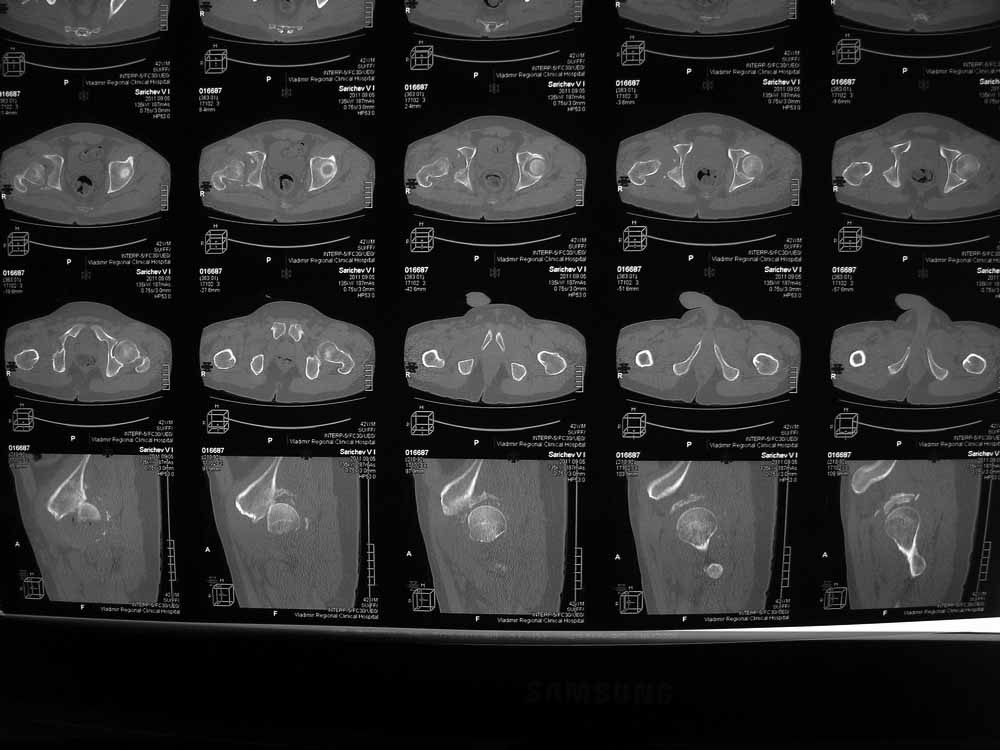

Вот еще сканы.

Структуру головки не очень хорошо видно, есть перелом нижнего отдела головки БК, сломанный задний край небольшой. Срок после травмы 4 недели, молодой возраст. Есть смысл синтезировать ВВ, а дальше посмотреть. Будут проблемы - легче будет протез ставить, ну а если лет 8-10 сустав поработает, то и это хорошо. Если вы уж решили делать протезирование, не мудрите, вполне можно обойтись стандартной вертлужной впадиной с укреплением ее винтами.

В этой ситуации предпочел бы эндопротез, шансы на жизнеспособность головки в таком сроке вывиха исчезающе малы, попытка синтезировать задний край в этих же сроках (ретракция мышц, рубцы) скорее всего приведут к его девитализации с последующим аваскулярным некрозом. Выбор вертлужного компонента проще планировать после 3D, скорее всего можно будет обойтись стандартными предложением, возможно, с котилопластикой.